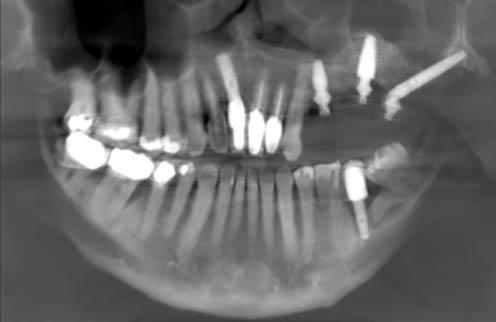

#13, #14 for ridge preservation. At a later date, three implant-supported crowns in close proximity were placed in these sites. Notably, the crowns were non-splinted. (Fig. 1).

In July 2021, the patient presented with mobile implants #12, #13 and #14 to his dental practitioner (Fig. 2). The implants were removed without bone grafting.

The patient received an interim removable partial denture and presented to the oral surgery clinic for evaluation for a fixed solution. At the time of initial consultation (September 2021), it was determined that failure of the implants was due in part to excessive occlusal forces as well as lack of proper hygiene maintenance and recall by the patient. For success, prior restoration design should have minimized difficult-to-reach areas for brushing

Fig. 1: May 2021. Panoramic radiograph shortly after placement of upper left #12, #13, #14.